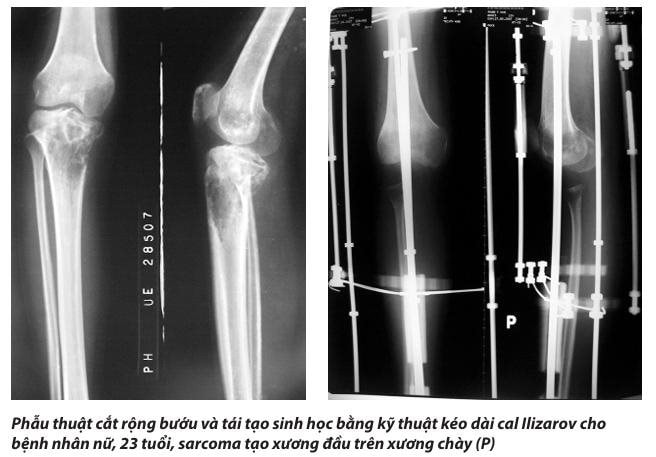

Ung thư xương nguyên phát, đặc biệt là sarcoma tạo xương (osteosarcoma) thường xảy ra ở trẻ từ 10–25 tuổi, tập trung ở vùng gần gối, xa khuỷu (tức là đầu dưới xương đùi, đầu trên xương chày, đầu trên xương cánh tay, đầu dưới xương quay). Nguyên nhân của sự phân bố này được lý giải bởi một số yếu tố sinh học và cơ học như sau:

- Phẫu thuật tái tạo lại khuyết hổng sau khi cắt bướu có thể sử dụng một trong 2 phương pháp: (1) tái tạo sinh học (như ghép xương, kéo dài cal xương, ghép xương tự thân tái chế…) và (2) tái tạo cơ học (thay khớp nhân tạo megaprosthesis).

TS.BS Lê Văn Thọ, Trưởng khoa Bệnh học Cơ Xương Khớp, Bệnh viện Chấn thương Chỉnh hình TPHCM sinh năm 1968. Tốt nghiệp bác sĩ đa khoa tại ĐHYD TP.HCM năm 1994. Tốt nghiệp chuyên khoa 1, chuyên ngành Chấn thương chỉnh hình (CTCH) năm 1999. Tốt nghiệp Thạc sĩ Y học, chuyên ngành CTCH năm 2003. Bảo vệ luận án Tiến sĩ Y học, chuyên ngành CTCH năm 2011 với đề tài: “NGHIÊN CỨU BẢO TỒN CHI BẰNG PHƯƠNG PHÁP TẠO XƯƠNG KÉO DÃN THEO NGUYÊN LÝ ILIZAROV TRONG ÐIỀU TRỊ UNG THƯ XƯƠNG VÙNG GỐI”.